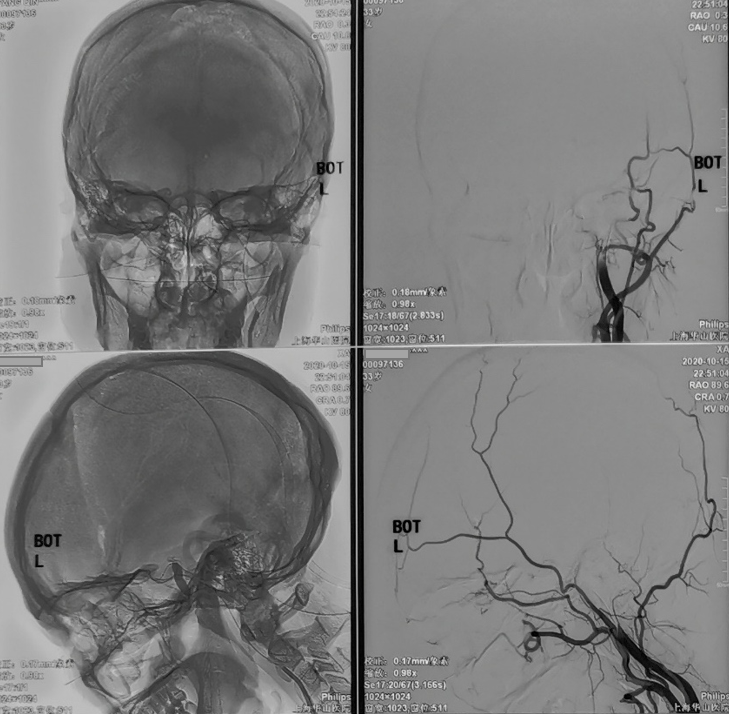

今天为大家分享的是,由复旦大学附属华山医院顾宇翔教授和倪伟医师带来的:巨大复杂颈内动脉分叉部动脉瘤一例,欢迎阅读、分享。

性别:女性,年龄:33 y.o